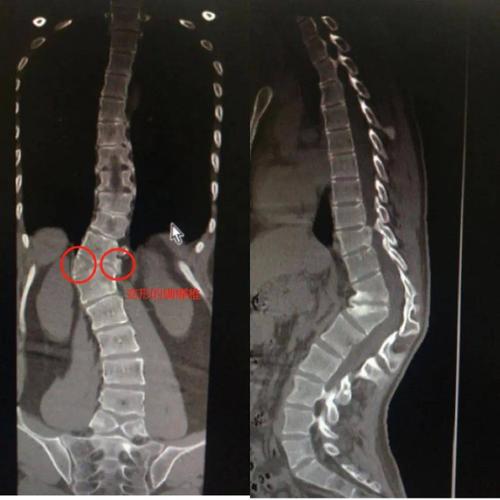

先天性脊柱后凸

先天性脊柱后凸,先天性脊柱侧凸

一例严重先天性脊柱畸形

讨论脊柱侧后凸畸形特点:1,多由先天性椎体畸形引起;2,发病率低但